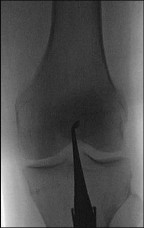

A 55-year-old man falls on his outstretched arm and sustains the injury shown in the 3-dimensional CT scans in Figures 1a and 1b.